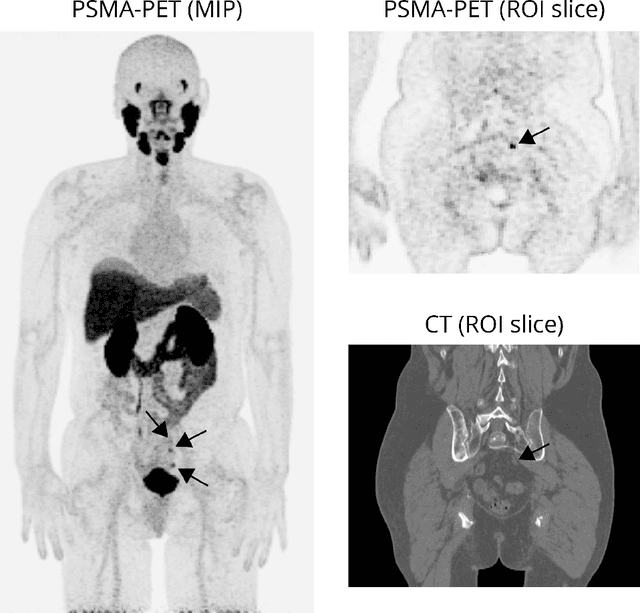

Abstract:Explainable artificial intelligence (XAI) is increasingly used to analyze the behavior of neural networks. Concept activation uses human-interpretable concepts to explain neural network behavior. This study aimed at assessing the feasibility of regression concept activation to explain detection and classification of multi-modal volumetric data. Proof-of-concept was demonstrated in metastatic prostate cancer patients imaged with positron emission tomography/computed tomography (PET/CT). Multi-modal volumetric concept activation was used to provide global and local explanations. Sensitivity was 80% at 1.78 false positive per patient. Global explanations showed that detection focused on CT for anatomical location and on PET for its confidence in the detection. Local explanations showed promise to aid in distinguishing true positives from false positives. Hence, this study demonstrated feasibility to explain detection and classification of multi-modal volumetric data using regression concept activation.